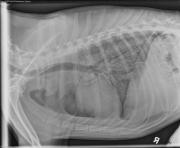

This week’s case is a 7-year-old male neutered mixed breed dog with lethargy, fever, lameness, and cutaneous lesions. How would you characterize this pattern?

R LAT Thorax

There is a diffuse micronodular interstitial pattern throughout the lungs. The trachea is dorsally deviated on the lateral projections, and there is increased soft tissue within the mediastinum. There is increased opacity in the region of the hilus with lateral deviation of the mainstem bronchi on the left lateral and ventrodorsal projections. Thin pleural fissure lines are visible.

The most likely differential diagnosis for nodular interstitial pulmonary pattern and thoracic lymphadenopathy is fungal pneumonia. Neoplasia and other inflammatory disease is less likely. Airway and lymph node sampling could be considered for cytology and culture.

• Blastomycosis was identified from smears of the skin lesions

• Previously moved from Iowa to California